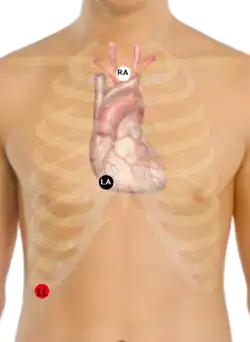

A Lewis Lead (also called the S5 lead) is a modified ECG lead used to detect atrial flutter waves when atrial flutter is suspected clinically, based on signs and symptoms, but is not definitely demonstrated on the standard 12 lead ECG. In order to create the Lewis Lead, the right arm electrode is moved to the manubrium adjacent to the sternum. Then the left arm electrode is moved to the right, fifth intercostal space adjacent to the sternum. The left leg electrode is placed on the right lower costal margin. The Lewis Lead is then read as Lead I on the ECG and, since in most patients it will be roughly perpendicular to the wave of ventricular depolarization, atrial flutter waves may be more apparent.